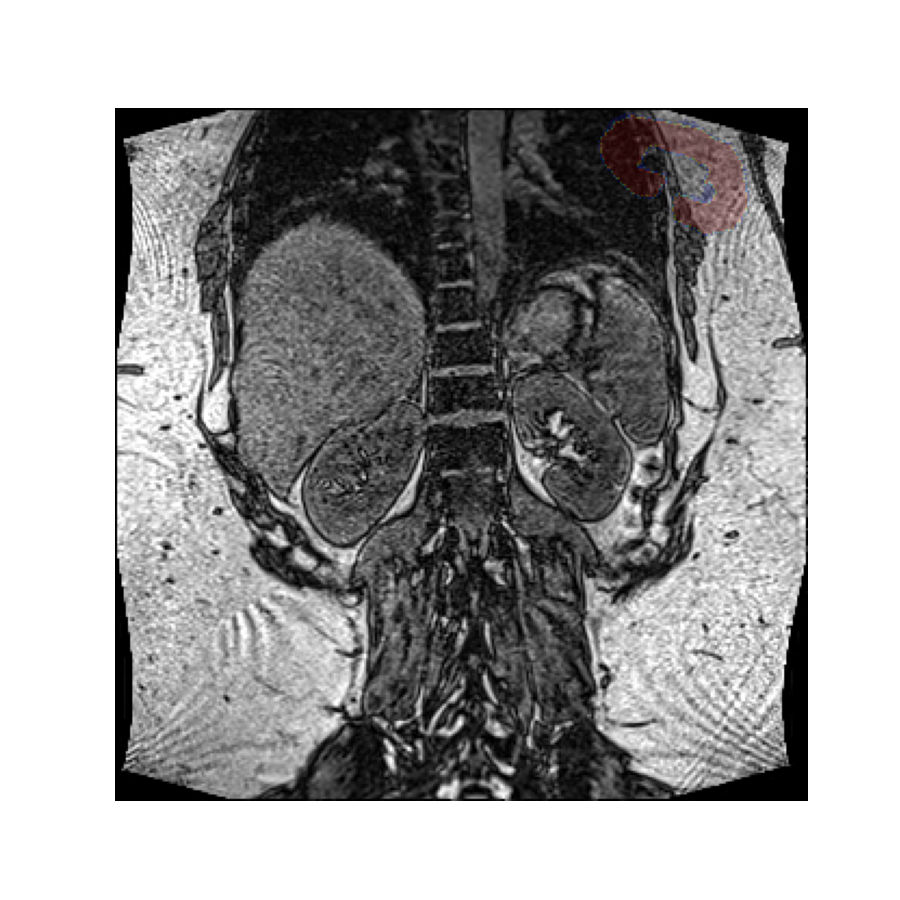

Without rotations, the mask aligns with the image:

plt.overlay_2d(img, mask)